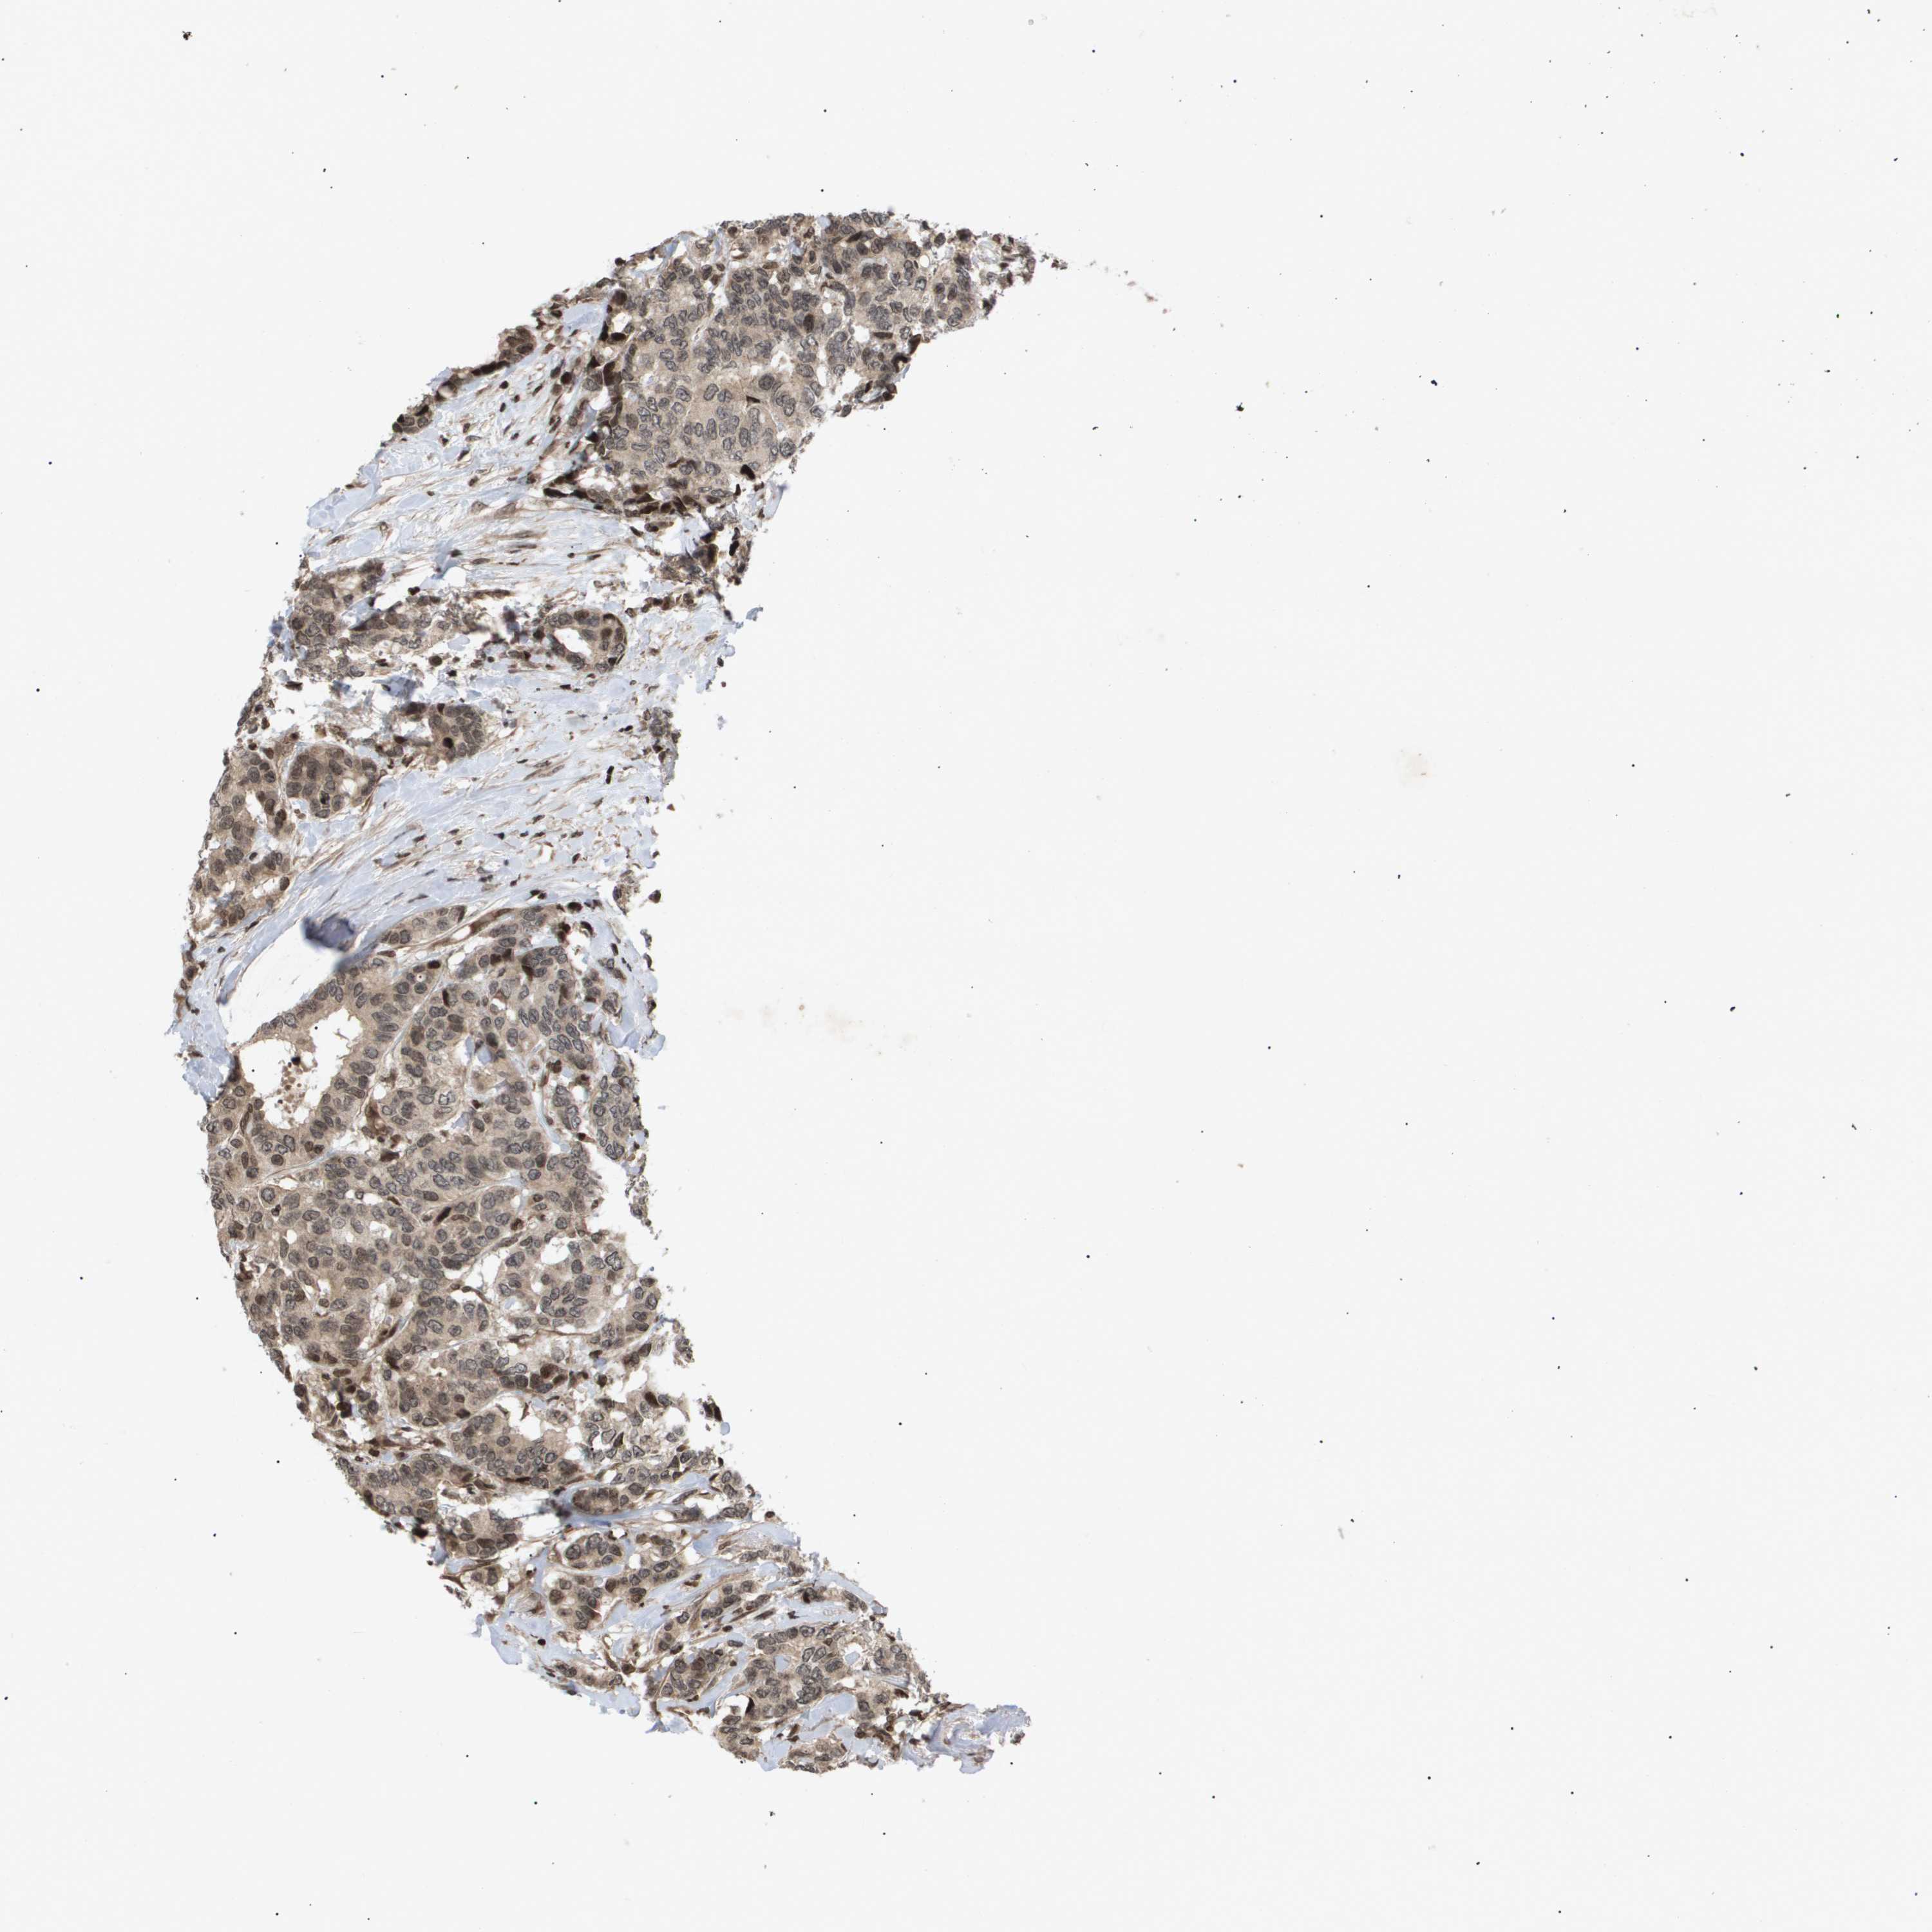

CANCER BREAST CANCER Show tissue menu

BRCA TCGA BRCA VALIDATION PROTEIN EXPRESSION

ANTIBODIES

AND

VALIDATION